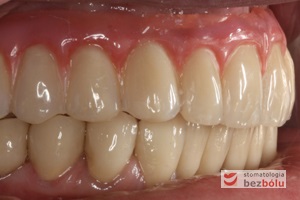

Ostateczny efekt estetyczny wieńczący proces terapeutyczny - odbudowa protetyczna obu łuków zębowych przy zastosowaniu implantów Friadent Ankylos

Ostateczny efekt estetyczny wieńczący proces terapeutyczny – odbudowa protetyczna obu łuków zębowych przy zastosowaniu implantów Friadent Ankylos